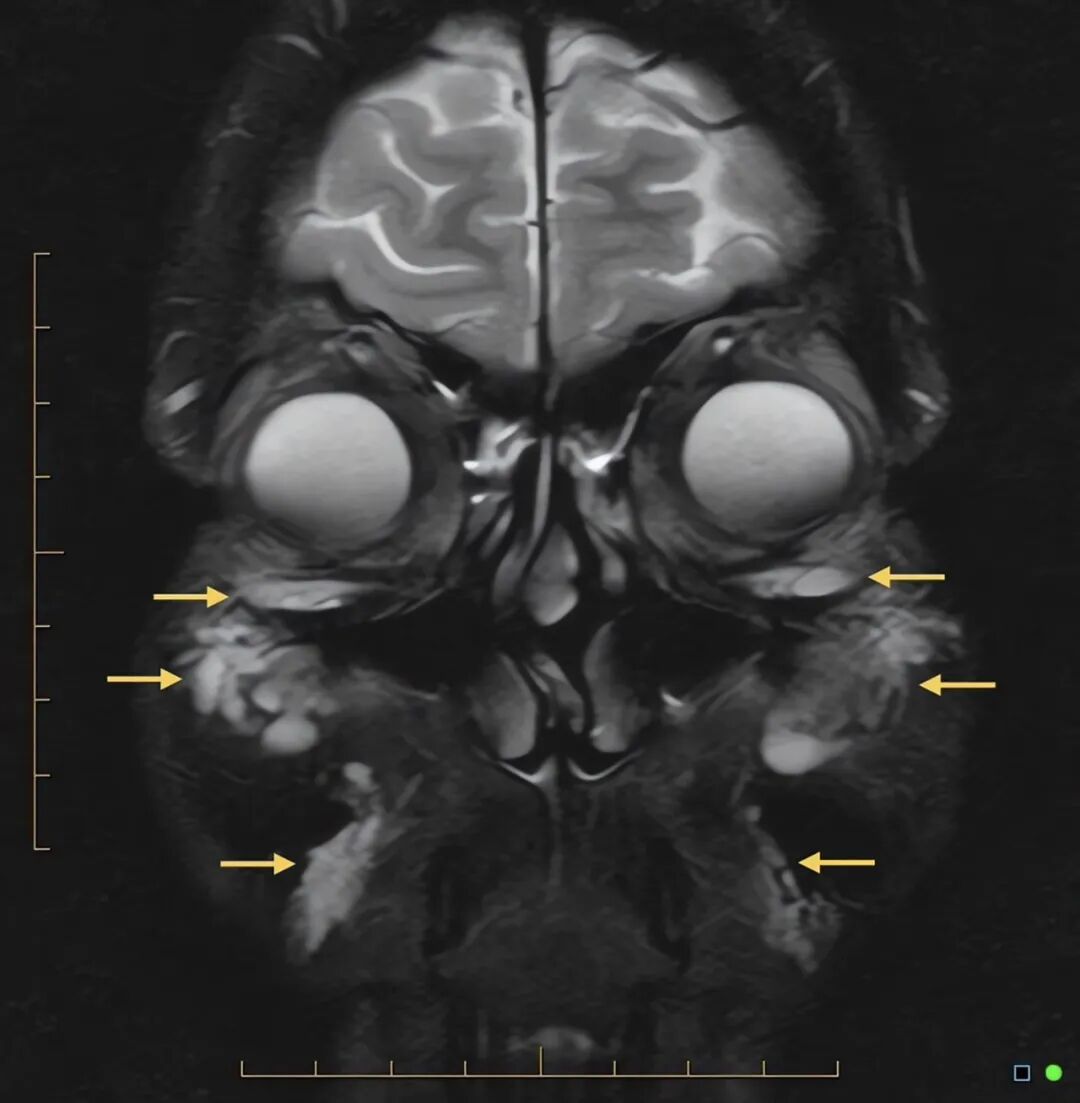

MRI研究证实,填充剂在注射多年后仍可能在影像学检查中显影。然而,MRI存在重要的局限。目前尚无标准化的透明质酸特异性成像方案,且T2高信号与水肿、炎症、积液的信号存在重叠。因此,影像学解读结果差异极大,且MRI无法对残留填充剂的含量进行定量分析。因此,影像学检查只能明确:填充剂的留存情况远比此前设想的复杂,且影像学检查结果不应被解读为临床治疗成功的定量或确定性标志(图4)。

图4. 冠状位 T2 加权磁共振成像(MRI),示眶下区、颧前区、面颊深部及木偶纹区可见多发 T2 高信号灶(箭头所示);上述信号符合残留透明质酸填充剂的影像学特征,但可与水肿或其他软组织积液的信号相重叠。